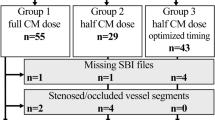

Sixteen different ROIs were used for the evaluation of the overall image quality in accordance with the latest PCCT studies [6]. Of those, nine ROIs involved the gray and white matter of the supratentorial cortex at different distances to the calvaria. The next six ROIs involved deep gray and deep white matter, namely the basal ganglia at two different locations superior and inferior, the thalamus and the immediately adjacent white matter in each case. Two ROIs were placed in the pons between the petrous bones to provide a measure of artifacts analogous to the preliminary studies [7]. The next ROIs were set in the acute hemorrhage, in the nearest gray matter, in the nearest nonpathologically altered white matter, and in the immediately adjacent white matter with possible pathological changes such as edema. Except for the ROI in the pons (200 mm2), all ROIs measured 4 mm2. Figure 1 shows the position of ROIs in hemorrhage and adjacent tissue.

Position of ROIs in hemorrhage and adjacent tissue. ROIs were set in the acute hemorrhage (1), in the adjacent white matter with possible pathological changes such as edema (2), the nearest gray matter (3), and in the nearest nonpathologically altered white matter. All ROIs measured 4 mm.2. Image of a VMI 66 keV with windowing C40/W80